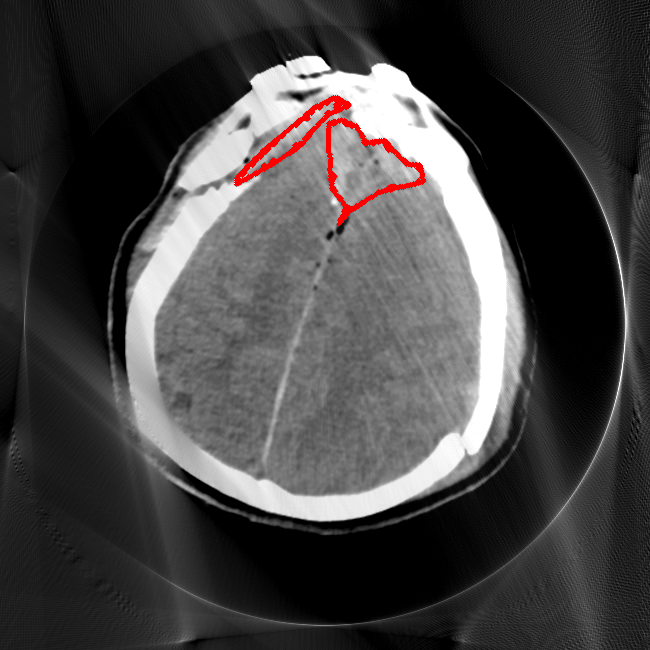

Limited Angle

CT GMAIMMbench Disease Diagnosis

Limited Angle - L0 (Original)

L0

L0 (Original)

Question

This is a CT image. Which of the following options is the most appropriate to demonstrate the marked area?

A brain hemorrhage B barrett's esophagus C thyroid nodule D retinal hard exudates

Ground Truth: A. brain hemorrhage